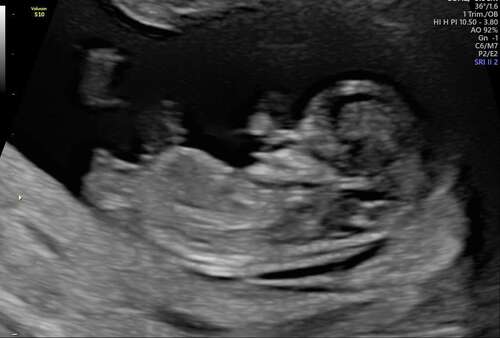

willen jullie met me mee kijken wat denken jullie dat het word ? 💙🩷❤️

Hoeveel weken? 12+ zeg ik meisje 🥰

11 weken 3dagen heb 2 foto's geplaatst vind je de andere ook een meisje?

Ja maar met deze termijn is dat heel normaal en kan het dus nog omhoog gaan en een alsnog een jongen blijken…